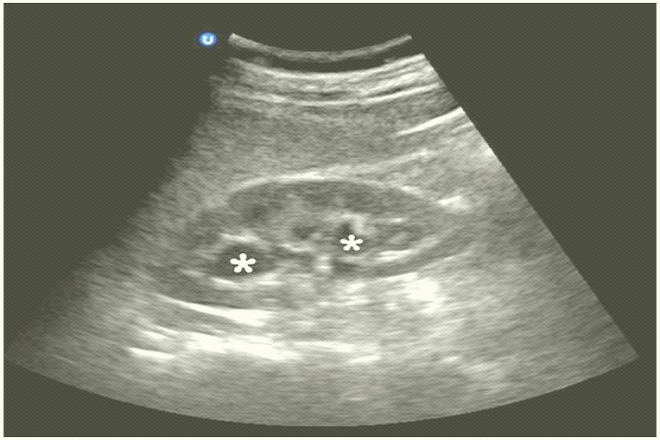

La ultrasonografía es esencial en la evaluación de patología renal aguda y crónica así como para realizar una biopsia. Por ello, los autores forman a sus médicos con adiestramiento en ultrasonido renal desde 1991, con principios habituales empíricos de la identificación del riñón normal en el niño y en el adulto. En la insuficiencia renal en fase aguda así como necrosis tubular aguda, registran riñones como normales, pero en cronicidad, disminuidos de tamaño con parénquima adelgazado, identificación de hidronefrosis de manera sensible, así como diagnosticar quistes. En hipertensión arterial secundaria, observan un riñón mayor que el otro (derecho > a 1,5cm, izquierdo > a 2cm) sugestiva de estenosis de arteria renal, que debe realizarse doppler, masas suprarrenales como en feocromocitoma, poliquistosis renal, siendo patológica en el 39% con función renal normal y de 69% en insuficiencia renal. En litiasis renal, imagen hiperecogénica con sombra acústica posterior, en mayores de 0,5cm, no sensible en las de ácido úrico donde es mejor placa simple, y en nefrocalcinosis cortical no así en la medular por la hiperecogenicidad del seno. En masas renales el límite en ultrasonido es de 2cm, sobre todo quistes, pero requiere para definición diagnóstica maligna la tomografía. En Biopsia renal es de elección el ultrasonido, siendo superior en el 90% de las series. Se usa en trombosis de vena renal, con doppler con inversión del flujo diastólico, también la estenosis de la arteria renal con más dificultad. Útil en transplante renal. El uso de contraste por medio de microburbujas llenas de gas para generar aumento en la señal del ultrasonido (< de 10 micras). Se inicia el perfeccionar catéteres tunelizados para hemodiálisis con transductor de alta frecuencia y doppler para localizar vena.

Se trata de la imagenología comparando dos grupos con todos los estudios que se efectúan en la actualidad, siendo el grupo A sin resonancia magnética y el B con resonancia magnética en cólico nefrítico por urolitiasis. En el grupo A, el ultrasonido logró detección de litiasis en el 58,22% y en densidad en el 24,02% con una correlación diagnóstica en el grupo A en general del 61,55% y en el B del 100%; en el líquido perinefrítico en el grupo B, asociado a la tomografía computada, identificación en 11,32% y de 2,53 sólo con ultrasonido. El ultrasonido juega un papel importante en la evaluación de la morfología y volumen renales, pero su sensibilidad para la detección de litiasis en bastante modesta, variando del 19 al 64% y de 74 al 85% en el diagnóstico de obstrucción, siendo su mayor desventaja que no puede dar una imagen completa del trayecto ureteral así que con la presencia de gas intestinal y en paciente obeso, se obtiene habitualmente una mala imagen. Por ello, en la actualidad el estudio para esta patología es la tomografía computada. Concluyeron que se considera por orden metodológico y algorítmico que la placa simple de abdomen y el ultrasonido deben ser los estudios primarios para el cólico nefrítico para la detección de litiasis renal en segmentos altos y bajos, la distención de la vía excretora asociada o no con líquido perinefrítico para determinar si se efectúa una tomografía o una resonancia.